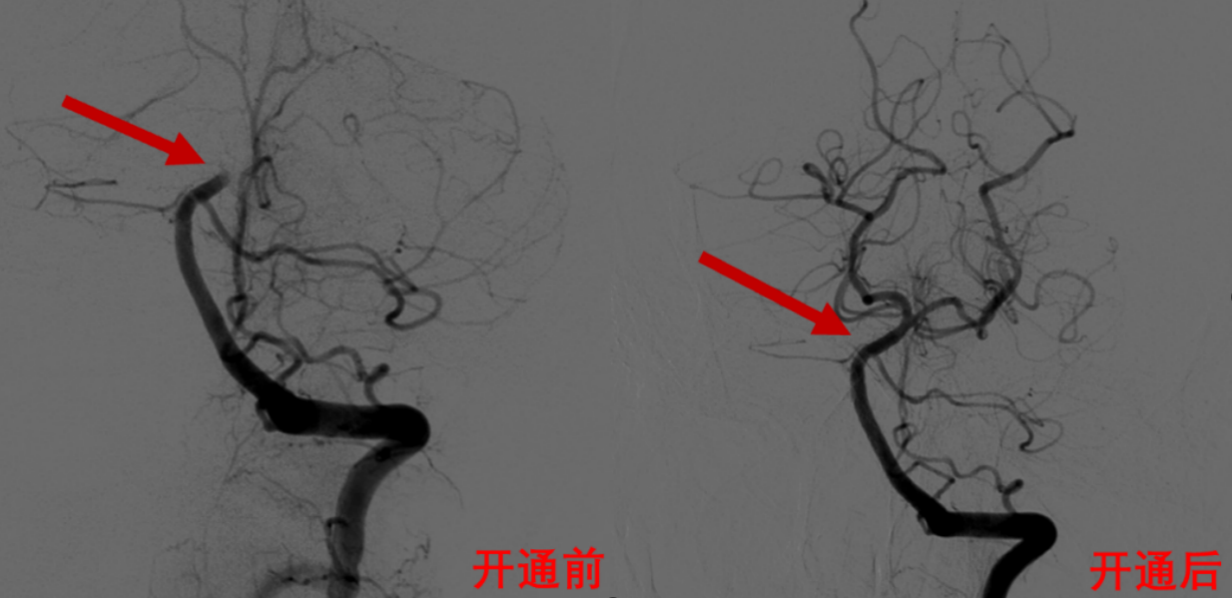

情况十分危急,唐先生很快就出现血氧饱和度下降,呼吸次数变慢。急诊科立即为他进行气管插管,并用呼吸机辅助呼吸维持生命。神经内科医生立即给予溶栓治疗,与此同时,介入导管室即刻开放,麻醉科迅速到位,脑血管病介入团队立刻给他进行脑血管造影术和基底动脉取栓术。

何旭英主任以及卢海克副主任医师通过脑血管造影,发现唐先生的脑血管状况非常差,手术难度高,右侧椎动脉先天发育不良,未汇入基底动脉,左侧椎动脉竟然也闭掉了。

“血管上不去,就没法做手术,更挽救不了患者的生命。”脑血管病介入团队当机立断,没有路也要开一条路出来,经过努力,开通了闭塞的椎动脉,并植入了支架保障血管持续的通畅性,再进一步将取栓器械直达基底动脉。

经过紧锣密鼓的手术、熟练干脆的取栓,团队很快取出基底动脉的一大块血栓,患者堵塞的血管重新开通了。